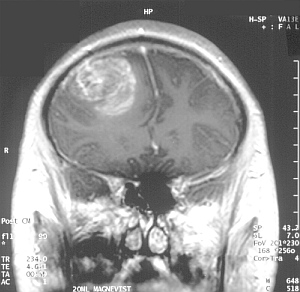

Glioblastom: Nanotechnologie ermöglicht neue Therapie (Foto: CC/Christaras A) |

Austin (pte030/21.03.2012/13:58) An der University of Texas http://utexas.edu erforscht man einen neuen Weg, Glioblastome gezielter und stärker zu bestrahlen. Dazu nutzt man Nanotechnologie, um andere Regionen des Gehirnes von den Auswirkungen der Strahlung zu verschonen. Das Verfahren hat in Tierversuchen vielversprechende Ergebnisse erbracht. Klinische Studien sind nun in Vorbereitung.